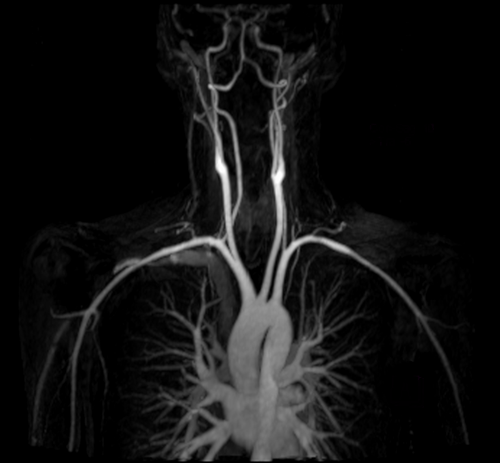

mri subclavian arm down mip 2 - MRI